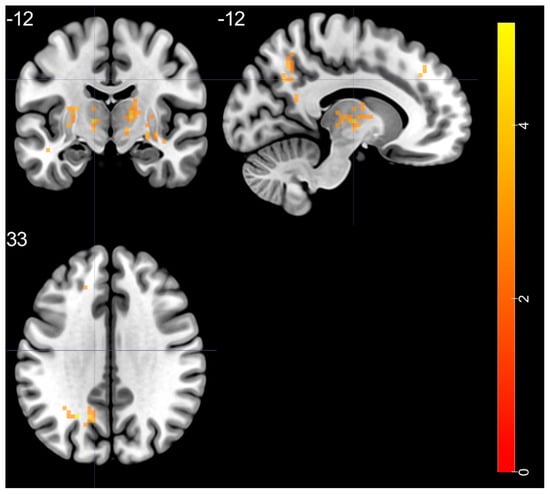

| Brain Regions | Peak T-Scores | MNI Coordinates | Cluster Size (Voxels) | ||

|---|---|---|---|---|---|

| x | y | z | |||

| BD > HC | |||||

| left STG—BA 20 | 4.525 | −48 | −24 | −6 | 38 |

| right putamen—BA 48 | 5.178 | 33 | −6 | 0 | 144 |

| right thalamus (ventral lateral nucleus) | 4.28 | 15 | −12 | 6 | 67 |

| left thalamus (ventral lateral nucleus) | 4.351 | −12 | −12 | 3 | 113 |

| left MOG—BA 19 | 5.075 | −24 | −60 | 33 | 58 |

| left SFG—BA 9 | 3.741 | −9 | 42 | 39 | 27 |